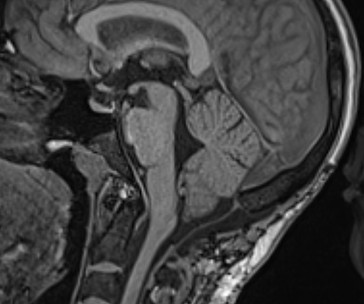

Chiari I malformācija

Pirmsoperācijas attēls. Redzama smadzenīšu noslīdēšana un saspiešanās ar muguras smadzenēm. Smadzeņu škidruma plūsma ir apgrūtināta.

Pēcoperācijas attēls. Redzama brīva telpa ap smadzenītēm, saspieduma vairāk nav. Smadzeņu škidruma plūsma ir netraucēta.